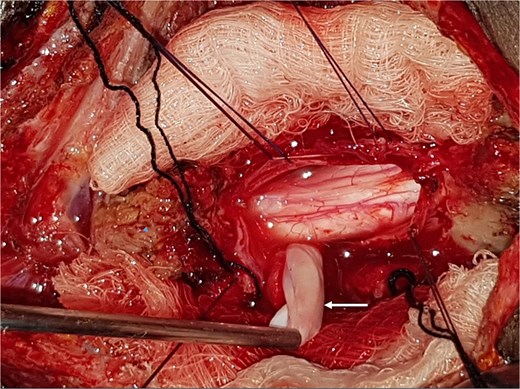

A 47-year-old man presented to us with progressive weakness of the extremities of 5 weeks duration. The weakness was first noticed in the left hand and progressed to involve the entire left upper limb and subsequently the right upper limb and the lower limbs. There was associated paraesthesia, constipation, and erectile dysfunction. Clinical examination revealed a middle-aged man with spastic quadriplegia and exaggerated muscle stretch reflexes. The sensory level was C4. Other systemic examination findings were normal. A clinical diagnosis of C4 non-traumatic myelopathy, Frankel B was made. Cervical spine MRI showed an intradural-extramedullary lesion with similar intensities to cerebrospinal fluid (CSF) on all sequences anterior to the spinal cord at C2–C4 with significant cord compression at C3–C4 and cord signal change on T2-weighted image at C2–C5 (Fig. 1). A diagnosis of cervical spine intradural AC was made. The lesion was accessed through C3–C4 laminectomies. At surgery, there was a cyst anterior to the cord with the latter flattened and displaced posteriorly. The cyst was excised completely and water tight dura closure done (Fig. 2). He made progressive post-operative neurological improvement and he was discharged on the 10th post-operative day. He was last seen 22 months post-surgery. At the time, he was ambulating without support, power was Grade 4+ to 5 in the upper and lower limbs.

Intra-operative photograph showing complete excision of the arachnoid cyst in Fig. 1.